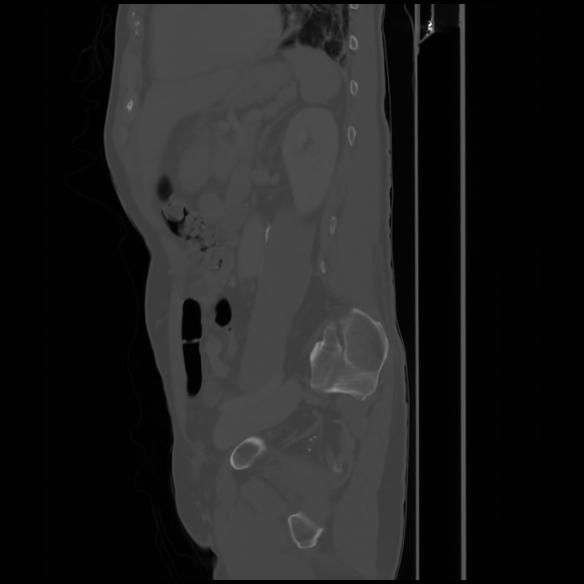

7 CUERPO,CE,Sagittal,3.000,CUERPO,Sagittal,